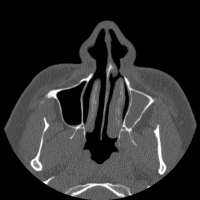

Here are a few shots illustrating how off-kilter my septum is. That line right down the middle is the septum, and it is supposed to be pretty straight. Mine, however, veers off to the left side of my body (the right in the pictures), includes a funky hook-shaped spur, and the whole nasal space is sort of off-kilter and asymmetrical. But it’s nothing that a little modern medicine can’t fix. The last picture has nothing to do with my septum, but I think it’s the coolest image on the my entire C/T scan disk.